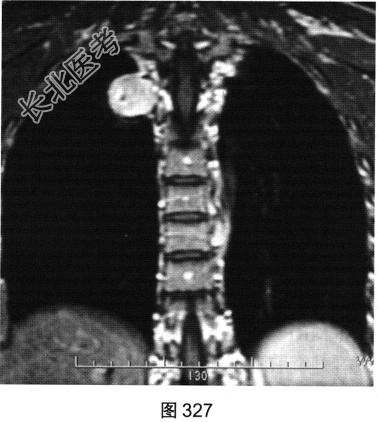

- [材料题] 患者女性,36岁,平素健康,无明显临床症状。单位体检拍摄胸部X线平片提示“右上肺阴影”。遂到大型医院进一步行胸部影像学检查,如图325~图327所示。

- 多项选择题2.关于该患者胸部MRI显示征象,正确的描述是( )

C、病灶位于右肺上叶后段胸膜下

D、病灶位于后纵隔脊椎旁区

E、在T,WI上呈高于肌肉的略高信号

F、在T2WI上呈高信号略欠均匀

G、冠状面示病灶可能来源于椎管内